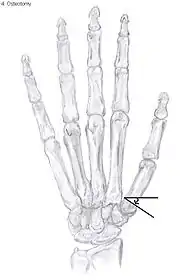

| Osteoarthritis of the trapeziometacarpal joint | |

Metacarpal osteotomy

The aim of metacarpal osteotomy is to change the pressure distribution on the TMC joint. The hope is that this will slow the pace of development of osteoarthritis. There is no evidence that this procedure can modify the natural course of TMC OA. Osteotomy may be considered for people with mild arthritis.[24]

During osteotomy, the metacarpal is cut and a wedge shape bone fragment is removed to move the bone away from the hand.[36] Postoperative, the thumb of the patient is immobilized using a thumb-cast.